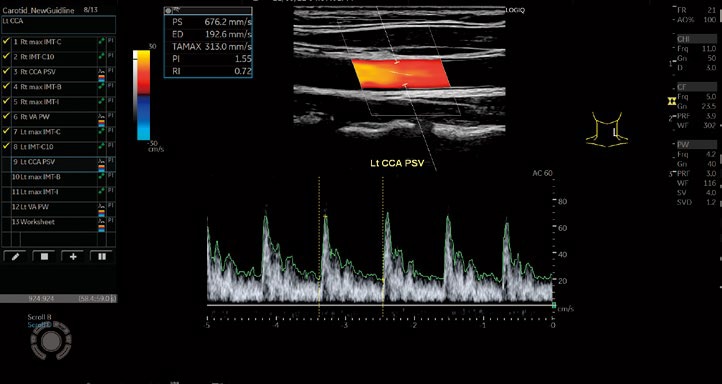

Auto IMT

自動で簡単にIMTを計測可能。

IMT-C10の計測もサポートし、検査の効率化に貢献します。